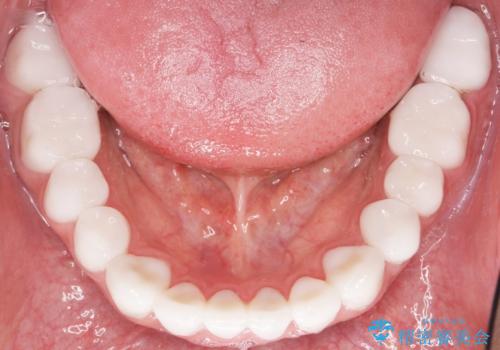

憧れの芸能人のような白い歯に 30代男性

- 憧れの芸能人(ヴィジュアル系バンドマン)のような歯になりたいとのご希望で来院された患者様です。

咬み合わせが悪く矯正も検討されていたそうですが、歯を真っ白にしたいというご希望もあり、28本のすべての歯をセラミックにしたいとのことでした。

精査したところ、ほとんどの歯が保険内のレジンで充填されており、咬み合わせも悪く咬合していない歯もありました。

虫歯をしっかりと治療したのち、オールセラミッククラウンによる補綴治療を行いました。

憧れのヴィジュアル系バンドマンのような白い歯になり、喜んで下さいました。

不適なレジン充填によるデコボコがなくなったことで歯磨きしやすくなり、また気にされていた咬み合わせも良くなり、ご満足頂けました。

クラウンの種類:オールセラミッククラウン スタンダード

シェード:NW0